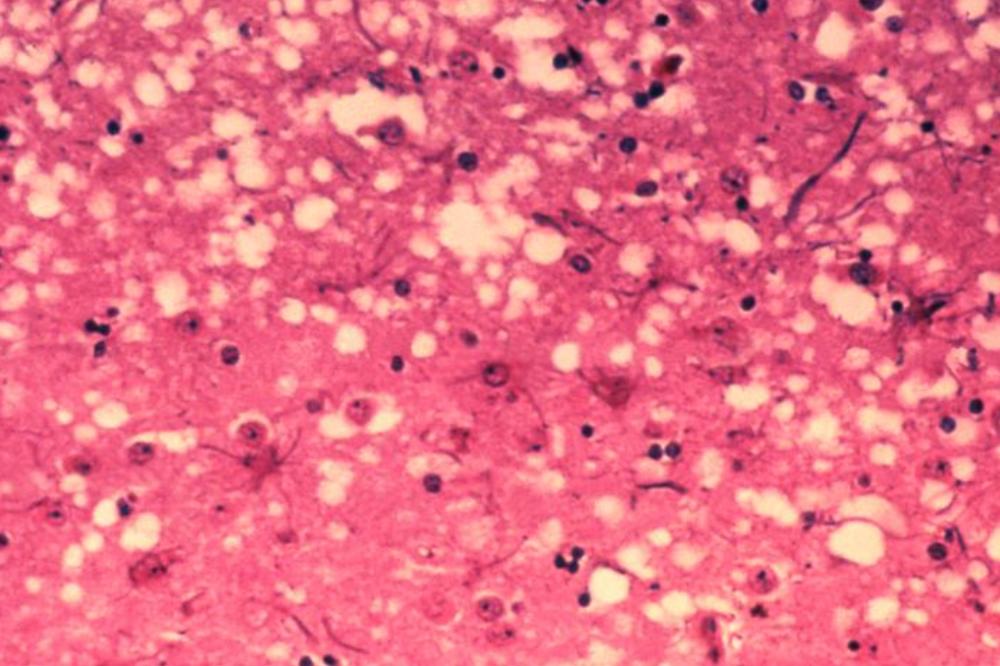

Prionske bolesti kao što je CJD uzrokovane su mutacijom gena. Ovi proteini imaju neobičnu sposobnost da konvertuju druge normalne prione tako da se presavijaju poput njih, sto pokreće jednu sporu kaskadu razaranja koja se širi mozgom i za sobom ostavlja karakterisične spužvaste mikroskopske rupe, koje se mogu videti u mozgu žrtve nakon smrti.